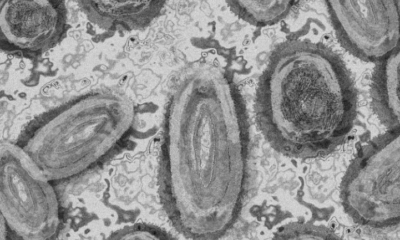

La viruela del mono ya llegó a Nuevo León en donde, este jueves, la Secretaría de Salud del estado confirmó el primer caso. El paciente es...